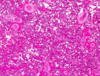

מהם המאפיינים ההיסטולוגיים של שחלות?

ovary

שחלה עטופה באפיתל גרמינלי חד שכבתי קובייתי

תחתיו של טוניקה אלבוגינאה- שכבה ורודה דקה של רקמת חיבור צפופה

סטרומה מאוד צלולרית- המון תאים. אופייני לשחלה

מה המאפיינים של הקורטקס והמדולה בשחלה?

קורטקס- זקיקים של השחלה, ביציות בשלבי התבגרות שונים

מדולה- שכבת חיבור רפה וכלי דם

אין בין שניהם גבול ברור.